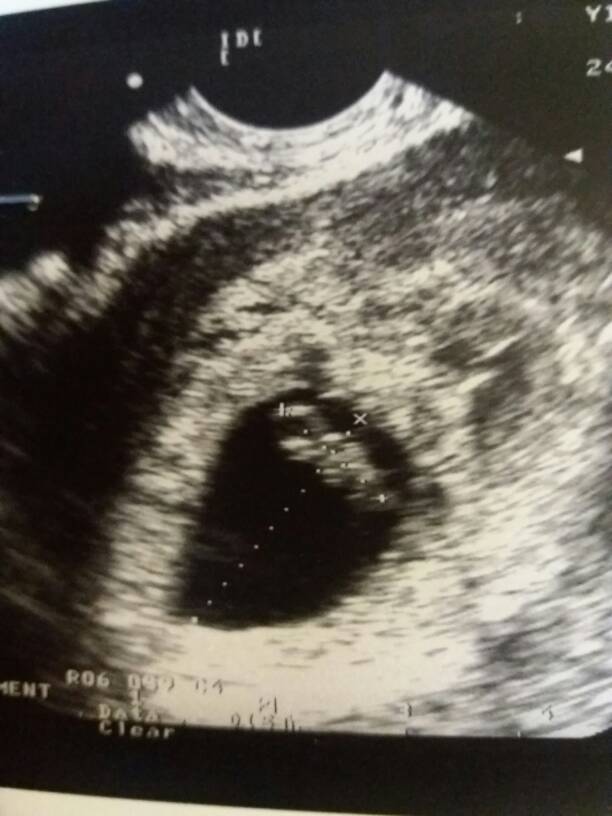

Dzidziuś ma się dobrze. Serduszka nie włączyła... chyba ma jakiś dziwny sprzęt :/ maleństwo ma 1cm i 20mm :) I już ładnie widać główkę i tułów :)